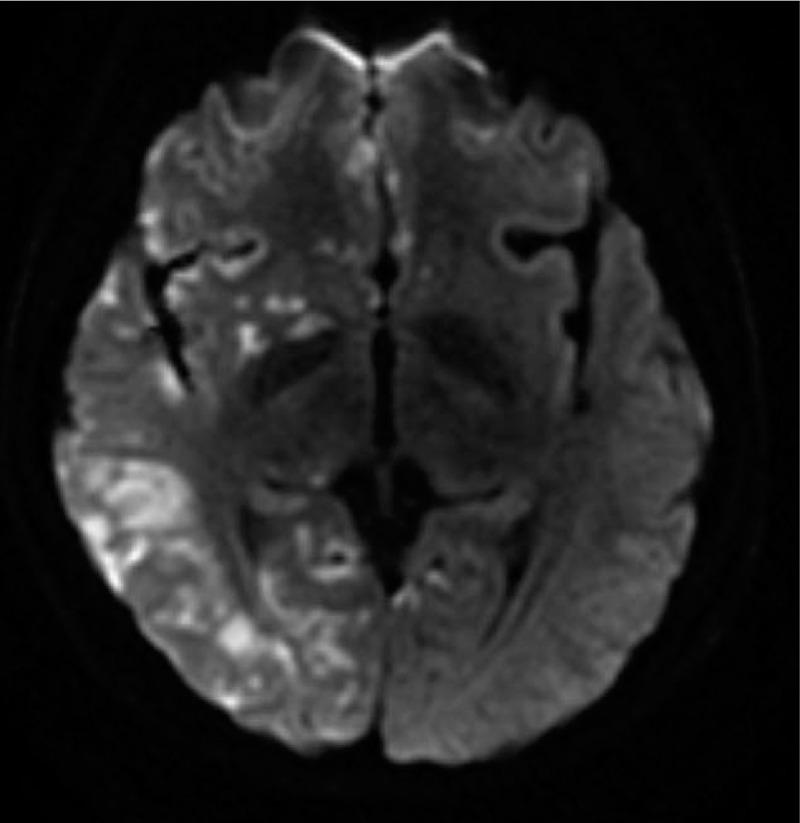

Cerebral carbon dioxide embolism after kidney cancer laparoscopic surgery with full neurological recovery: A case report.

Cerebral carbon dioxide embolism (CCDE) is a rare cause of stroke and is a recognized life-threatening complication.CCDE may result from direct intravascular CO2 insufflation during surgery. Due to the lack of typical clinical manifestations, the disease is often missed or mistaken for another condition. The clinical signs and symptoms depend on the speed and volume of embolized gas entering the blood and the patient's condition. In particular, patent foramen ovale has been found to be associated, in rare cases, with the intraoperative entry of gas into the arterial system.

In this report, we present the case of a 35-year-old woman with kidney cancer who underwent laparoscopic right partial nephrectomy.

After the laparoscopic surgery, the patient was initially diagnosed with acute cerebral infarction.